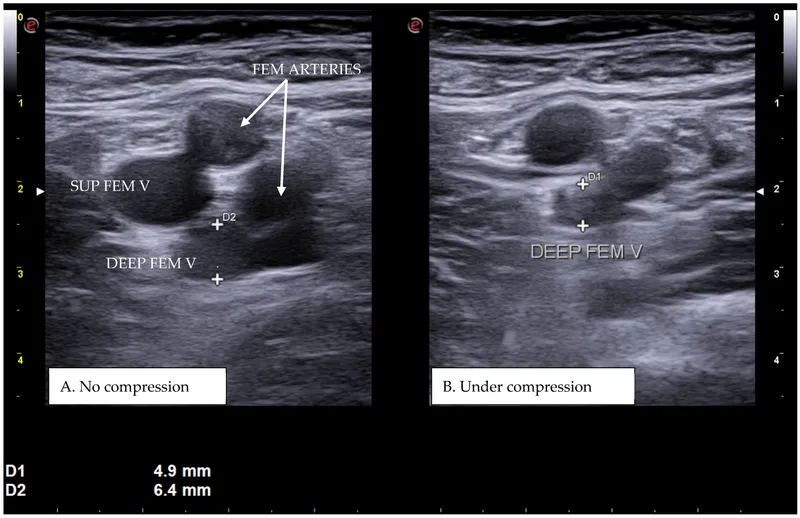

| Ultrasound | Dynamic assessment | 70-85% | 80-90% | 2x | None |

Vascular Injury Patterns